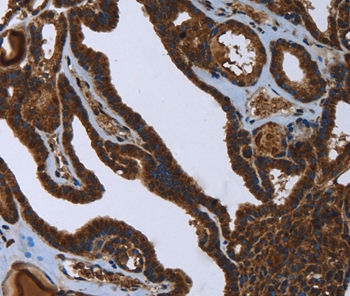

Immunohistochemical analysis of paraffin-embedded Human thyroid cancer tissue using #36470 at dilution 1/45.